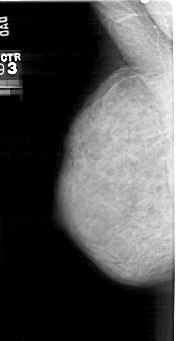

A_1342_1.LEFT_MLO

DATE_OF_STUDY 10 2 1993

PATIENT_AGE 41

DENSITY 4

LEFT_MLO LINES 5101 PIXELS_PER_LINE 2641 BITS_PER_PIXEL 12 RESOLUTION 43.5 NON_OVERLAY